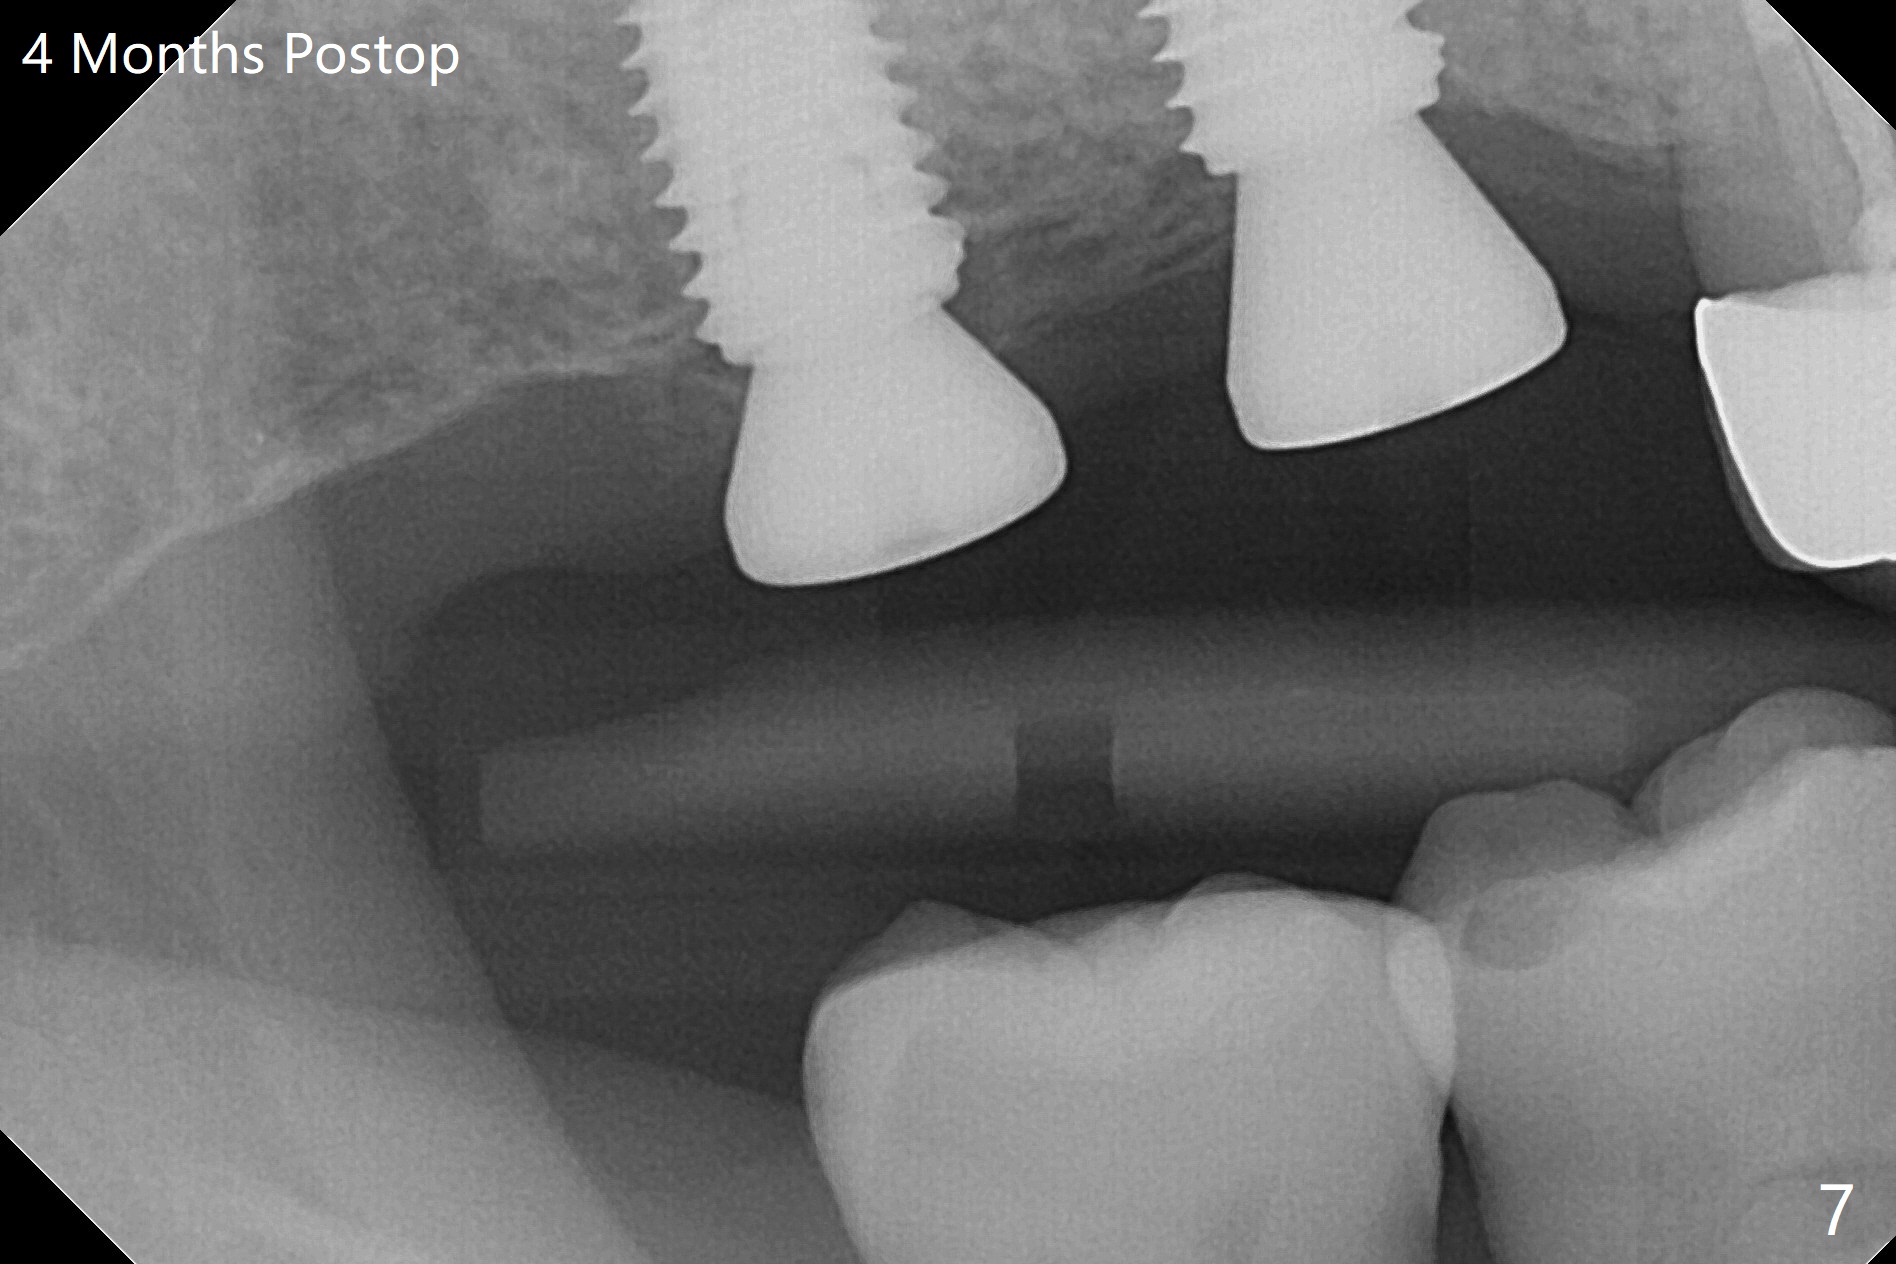

Two of 5x8.5 mm implants are placed at #2 and 3 with sinus lift using water ballooning technique; to avoid invading the neighboring root tips, an intraop PA is taken with a 2.2x11.5 mm drill at #5 (Fig.1). When a 2.5x11.5 mm 1-piece implant is placed at #7, there is 2.4 mm clearance from the impacted tooth (Fig.2). Following 1 mm deeper placement of the 1-piece implant, CT is taken to make sure that the threads are completely covered palatally (Fig.5 P). Interesting is that the sinus membrane is thickened at #2 and 3 (Fig.3 M), as compared to the clear sinus before surgery (Fig.3'). Bone graft is limited in the sinus (Fig.3 arrowheads). The implant at #5 (3.5x11.5 mm) is precisely placed subcrest bucco(B)-palatally (Fig.4). Since the limited field viewed CT does not cover the implant at #2 (Fig.3), immediate postop PA is taken (Fig.6). In fact all of the implants are placed subcrestal, as shown by intraoral X-ray 4 months postop (Fig.7-9). The abutments at #2, 3 and 5 are retorqued (30 Ncm) after crowns' try in and adjustment (Fig.10,11). There is a vertical gap between the implant and abutment at #2 (Fig.11 ^) and a horizontal one at #5 (<). There is apparently no bone loss 1 year 5 months post cementation (Fig.12).